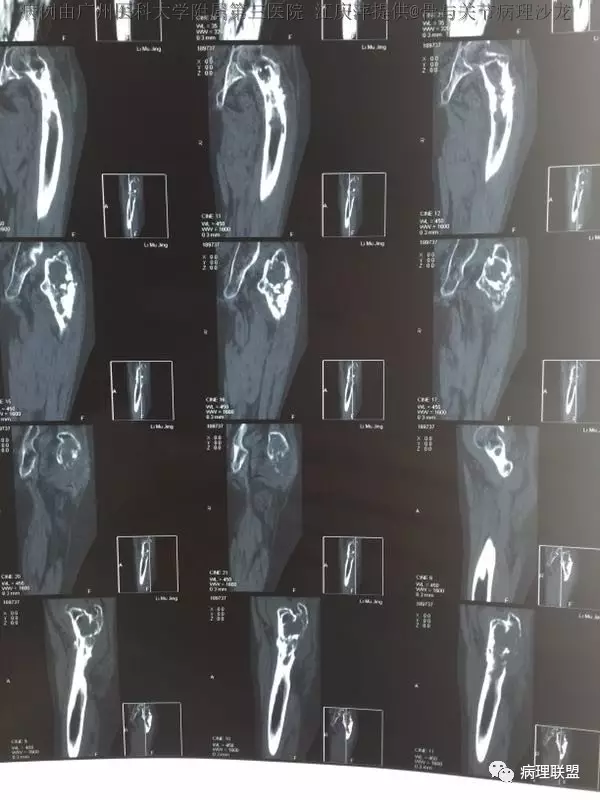

女,63,反复髋关节疼痛30年,活动受限2周(病例由广州医科大学附属第三医院 江庆萍提供,致谢)